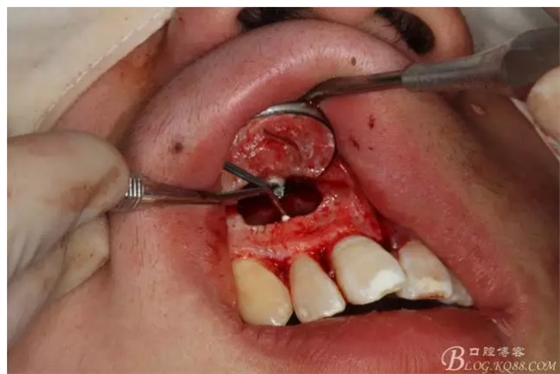

圖4.摘除囊壁后形成的巨大骨腔

圖5.清理骨腔,可以看到12的根尖暴露在骨腔內(nèi)。